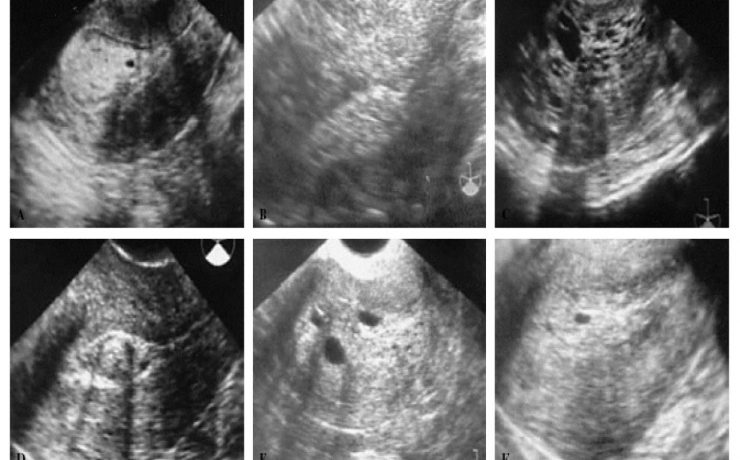

El nódulo tiroideo, es una entidad patológica muy frecuente, con una prevalencia estimada de 4 a 7% por palpación en relación 5:1 en mujeres. Un nódulo tiroideo de más de 1 cm de diámetro por lo general es palpable. Sin embargo, la detección de un nódulo por palpación dependerá de